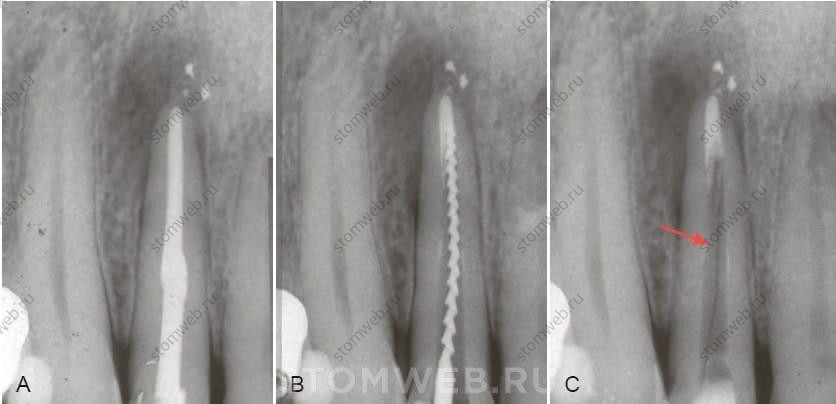

Иногда окончательный диагноз вертикального перелома корня может быть поставлен при наличии тонкой линии просветления на рентгенограмме вдоль корня. Такую линию однако обнаружить нелегко, на регулярных прицельных рентгенограммах она обычно не видна либо из-за маскировки корневым пломбировочным материалом, либо если угол съемки не оптимален для обнаружения перелома (см .рис. 21-13) (Рис. 21-20 и 21-21). Rud и Omnell показали, что при видимости линии перелома в 35,7% случаев, многие из этих случаев тем не менее не являлись истинными вертикальными переломами корня. На практике все еще редко вертикальный перелом корня обнаруживается на рентгенограммах, особенно если проводится единичный прицельный снимок. При этом плоскость перелома не должна совпадать с плоскостью датчика и линия перелома не должна перекрываться корневой пломбой (рис.21-20, А). Следовательно, при подозрении на перелом, следует сделать два или три снимка под разными углами (см рис. 21-21 и 21-22)

РИС. 21-20 Рентгенограмма пустого канала ex vivo. Левый второй нижний премоляр был лечен эндодонтически без использования штифта. Через тринадцать месяцев пациент начал жаловаться на боль и чувствительность при дотрагивании с язычной поверхности. Рентгенограмма не показала ничего необычного (А). С язычной стороны был обнаружен изолированный карман глубиной 7 мм и зуб был удален. На щечной (В) и язычной (С) поверхностях средней трети корня видны вертикальные переломы. Рентгенограмма после удаления также без признаков дефекта (D). После удаления корневой пломбы были сделаны рентген снимки под разными углами (E,F). На одном из них четко виден вертикальный перелом корня (F).

РИС. 21-21 Рентгенограмма пустого канала: клинический случай. Правый верхний латеральный резец был лечен по поводу осложненного кариеса несколько лет назад. Пациент жаловался на периодические боли с небной стороны. Реакция зуба на перкуссию и пальпацию с небной поверхности положительная. На рентгенограмме обнаружен периапикальный очаг просветления (А). С небной поверхности корня был обнаружен глубокий узкий единичный карман. И пациент, и врач не хотели удалять зуб, предположив, что карман, возможно, является свищевым ходом, и приняли решение перелечить канал. Рентгенограмма с файлом в процессе лечения (В) могла скрыть важную информацию, которую заслонил файл, а именно очевидный вертикальный перелом корня (С).

Рентгенография незаполненного канала

Как уже говорилось, обнаружение вертикального перелома корня на ранней стадии на прицельной рентгенограмме маловероятно, особенно если канал зуба запломбирован. Так как большинство переломов возникает в щечно-язычной плоскости, их просвет на рентгенограмме маскируется корневой пломбой (см. рис. 21-13 и 21-20). При подозрении наличия вертикального перелома корня можно начать перелечивание корневого канала, провести дезобтурацию и сделать несколько рентгенограмм под разными углами. При обнаружении тонкой линии просветления можно с большей уверенностью ставить диагноз вертикальный перелом корня (см. рис. 21-20 и 21-21).